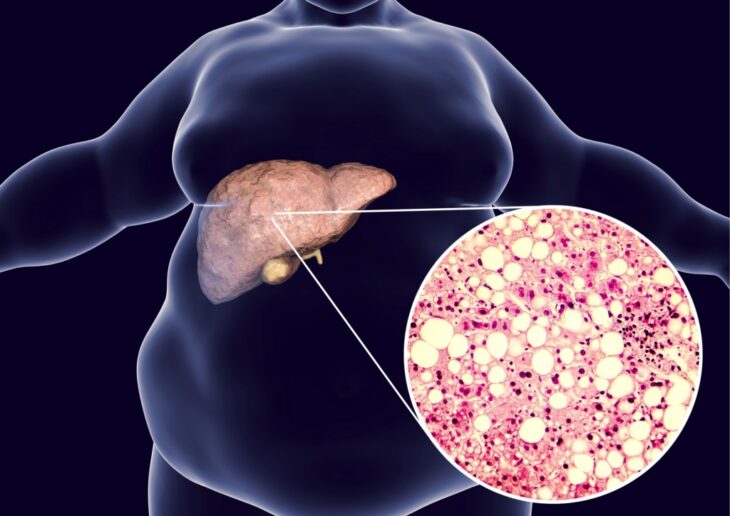

Recomienda IMSS Veracruz Norte alimentación saludable para prevenir hígado graso

Xalapa, Veracruz, a 26 de diciembre de 2025 Con el objetivo de prevenir complicaciones en la salud y mantener una saludable función hepática, el Instituto Mexicano del Seguro Social (IMSS) […]